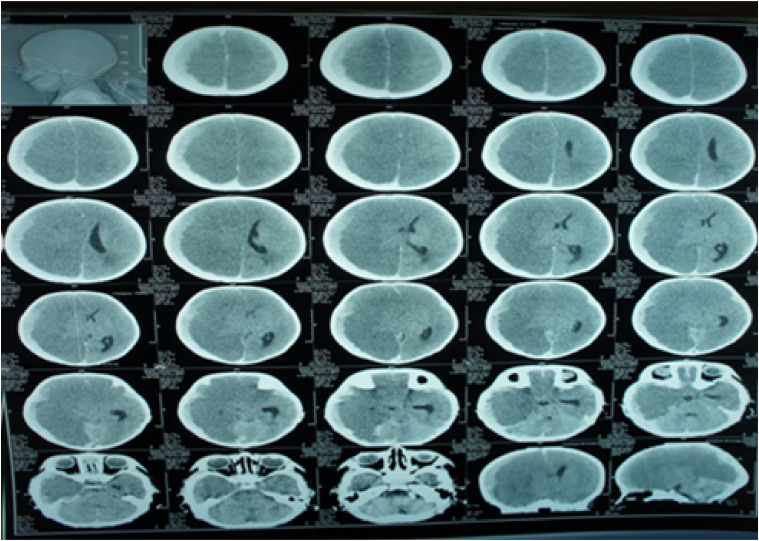

Abstract Image